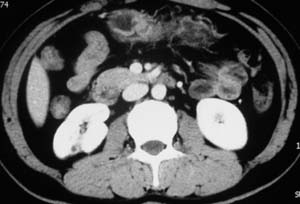

以下是引用子期在2010-3-19 20:47:00的发言:[br]血管畸形的ct增强应该有明显强化,本例并不相符合。本例双肾局部的略低密度影,累及肾盂,局部皮质明显变薄、内陷,增强扫描有轻度的强化,应考虑为炎性病变,患者为年轻男性,累及双肾的感染以结核较常见,可以没有明显的临床症状,尿中有时候也并不能查出什么;肾脓肿常有明显感染中毒症状,本例不符,另外一般的肾盂肾炎或肾小球肾炎通过小便就可确诊,其它还不能排除的是黄色肉芽肿性肾盂肾炎,然而单凭ct一般也很难鉴别。